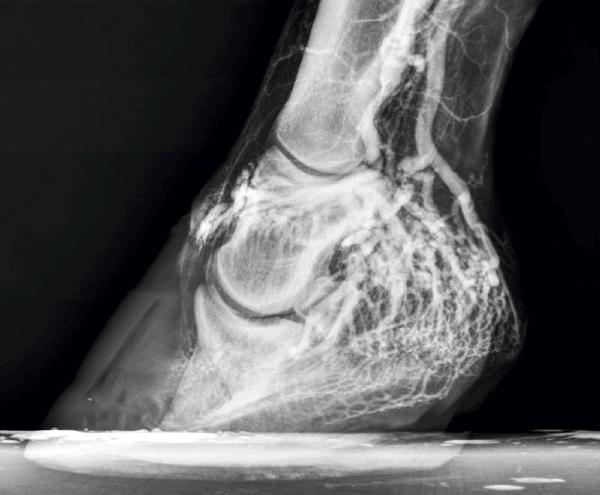

Recently I received a call out to a horse that had been on a hack through a forested area. While crossing a river, he had sustained a deep laceration to the back of the pastern on a front leg which presumably had been caused by a sharp stone. The horse pulled up lame immediately and the wound was bleeding.

The owner was luckily not far from home and was able to walk the horse back to the stable in hand. She cleaned the wound as well as she could with hose water and disinfectant and applied a pressure bandage as there was still a lot of bleeding. She then called me for help.